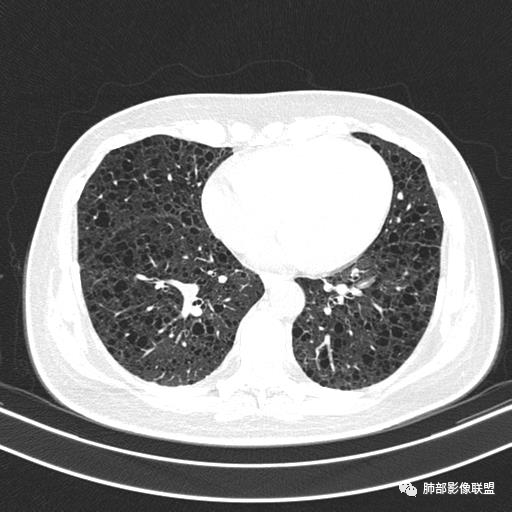

中年女性,不吸烟

双肺弥漫囊腔,累及肋膈角,囊腔形态相对规则单一。

CT平扫示双肺弥漫分布大小不等囊状薄壁透光区,无内、中、外带分布差异,间质稍示增厚。拟LAM

中年女性育龄期妇女,咳嗽气喘,无吸烟史,有苯吸入史。影像:双肺弥漫均匀小囊腔,无明显分布优势,囊腔形态欠规则,壁薄,部分囊腔边缘血管征,伴双肺弥漫磨玻璃影,无结节,考虑lam,鉴别苯中毒肺损伤,囊腔多有分布优势,小叶中心分布为主,形态规整等

女,46,活动性气喘1年。苯吸入史半年。胸部CT:两肺弥漫囊腔,上至肺尖,下至肋膈角,形态类似小囊腔。考虑:LAM,鉴别LIP,BHD,PLCH等。

双肺弥漫大小不一薄壁含气囊腔,囊间肺组织正常,正常肺背景,肺尖肺底受累;青年女性,气喘,支持LAM

双肺多发大小相近的囊状影,分布趋势趋于一致,中年女性,考虑LAM。部分囊内见血管及分隔影,小叶中心性肺气肿代排

CT表现:双肺弥漫大小不等的薄壁囊腔,囊壁<2mm,外形规则,血管影多位于囊腔周围,囊腔之间肺组织正常,随着疾病进展到晚期,囊腔变大、增多,不可胜数,囊腔可融合成较大的囊,与肺气肿相似,形成间质性肺纤维化。部分病例可出现结节影。